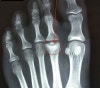

X-ray에서 골두의 편평화, 경화나 분절이 나타납니다.

X-ray : 프라이버그씨 병(Freiberg’s disease)